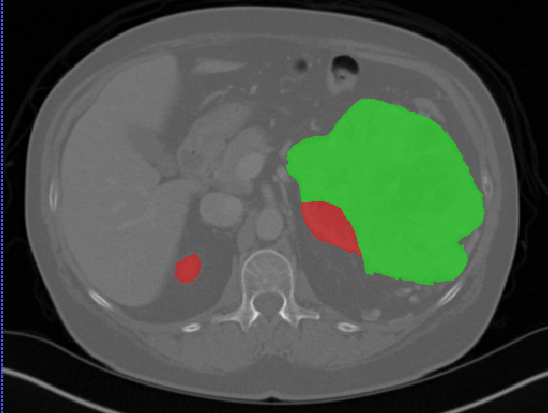

Edge-Aware 3D Image Segmentation Networks

[91]: Automated segmentation of kidneys and kidney tumors is an important step in quantifying the tumor’s morphometrical details to monitor the progression of the disease and accurately compare decisions regarding the kidney tumor treatment. Manual delineation techniques are often tedious, error-prone and require expert knowledge for creating unambiguous representation of kidneys and kidney tumors segmentation. We propose a 3D end-to-end edge-aware FCN for reliable kidney and kidney tumor semantic segmentation from arterial phase abdominal 3D CT scans. Our segmentation network consists of an encoder-decoder architecture that specifically accounts for organ and tumor semantics. We evaluate our model on the 2019 MICCAI KiTS Kidney Tumor Segmentation Challenge dataset. -

Kidney and Kidney Tumor Segmentation

Kidney cancer accounted for nearly 175,000 deaths worldwide in 2018 [13], and it is projected that 14,770 deaths will occur due to the disease in 2019 in the US [111]. Current kidney tumor treatment planning includes Radical Nephrectomy (RN) and Partial Nephrectomy (PN). In RN, both the tumor and the affected kidney are removed whereas in PN the tumor is removed but kidneys are saved [116]. Although RNs were historically prevalent as a standard treatment procedure for kidney tumors, new capabilities for earlier detection of the tumors as well as advancements in surgery has made PNs a viable treatment approach [53].

Traditionally, various techniques such as deformable models [86], GrabCuts, region growing and atlas-based methods have been applied to the problem of kidney segmentation. In recent years, researchers have attempted to leverage the power of deep learning and CNNs to build segmentation frameworks that are more automated and less dependant on incorporation of prior shape statistics. Thong et al. [119] proposed a 2D patch-based approach for kidney segmentation in contrast-enhanced CT scans by leveraging a modified ConvNet.

Jackson et al. [62] developed a framework for detection and segmentation and of kidneys in non-contrast CT images by utilizing a 3D U-Net. Yang et al. [128] proposed a method for kidney and renal tumor segmentation in CT angiography images by a modified residual FCN that is equipped with a pyramid pooling module. Furthermore, Yin et al. [130] employed a cascaded approach for segmentation of kidneys with renal cell carcinoma by training a CNN that predicts a bounding box around the kidney and a subsequent CNN that segments the kidneys. Recently, Xia et al. [126] proposed a two-stage approach for the segmentation of kidney and space-occupying lesion areas by using SCNN and ResNet for image retrieval and SIFT-flow and MRF for smoothing and pixel matching.